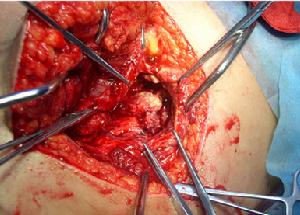

(3)寒性膿腫:骶髂關節結核時,如膿液聚集在髂腰韌帶下可沿腰大肌流至大腿;亦可由坐骨大孔穿出至臀大肌深處由梨狀肌下方沿坐骨神經下行至大腿後部或大轉子處;少數情況下感染可蔓延至坐骨直腸窩。